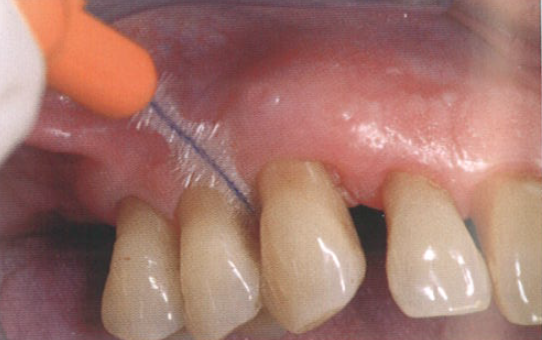

临床医师将大量具有致病性的病原菌的生物膜去除,从而阻断了由菌斑诱导的牙周炎症的复发。除了让患者在家中遵循更有效的清洁程序外,还建议使用半导体激光(图2)。

图2  使用半导体激光处理牙周

使用该半导体激光的目的是杀菌,并与常规的牙周非手术刮治相结合。在4个月后的随访复诊中,用轻柔的力量进行探诊,探诊深度稳定在大约5 mm,无探诊出血。